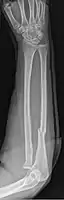

- Monteggia fracture - a fracture of the near to elbow end of the ulna with the dislocation of the head of the radius at the elbow joint.[2]

Monteggia Fracture (fracture of proximal ulna)

Galeazzi facture (displaced fracture of the radius)